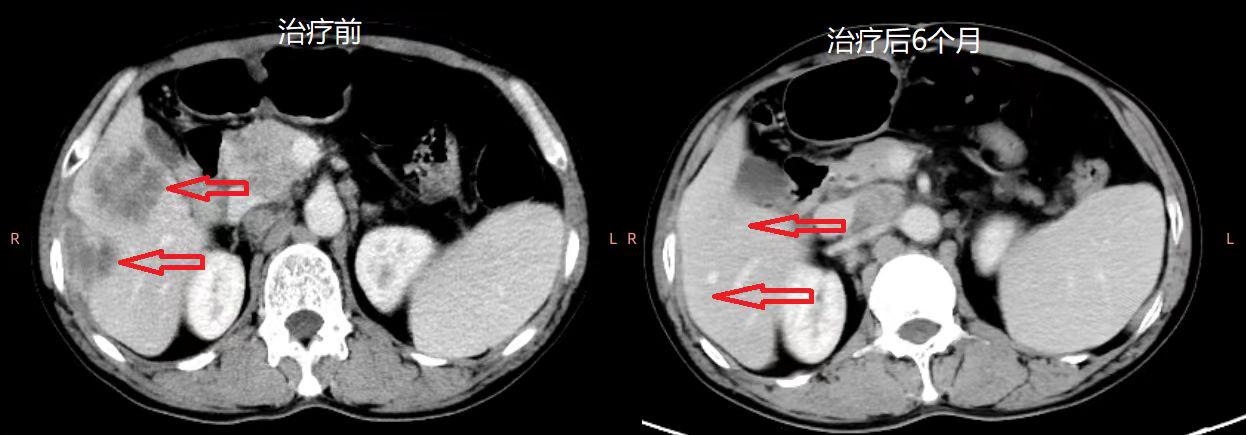

截至目前,共入组13例多线治疗后的晚期结直肠癌患者,并接受了CAR-T治疗,其中10例可评价。这10例患者中,6人病情得到了缓解,2人病情稳定,2人出现了疾病进展,均未出现严重的不良反应事件。其中一名患者在观察的近9个月时间内无任何其它抗肿瘤治疗,肝功能等生化指标有所改善,病情一直稳定无进展,个人生活质量也得到了提高,情绪也有好转。复查的CT结果显示肝和肺转移灶也显著减少,肿瘤缩小的总体积达40%(如下图2)。

图2 肝部和肺部肿瘤缩小情况前后对比图